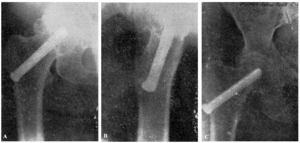

Con buena técnica, todos los resultados son favorables, a pesar de que al cabo de algunos años exista un grado más o menos acentuado de artrosis (véanse la observación núm. 4, fig. 7., A y B, y la observación núm. 9, fig., 8. A, B y C), que corresponden a los dos enfermos que hace más tiempo que están operados, y que en la actualidad aún viven.

Figura 7. A: obs. núm. 4. Enfermo de sesenta y cuatro años, operado en noviembre de 1935. La situación del clavo puede aceptarse como buena (ligeramente craneal). B: obs. núm. 4. Radiografía del mismo enfermo de las dos figuras anteriores, practicada en la actualidad (julio de 1943). Artrosis manifiesta. La cabeza del fémur tiende a aplastarse. Deambulación perfecta.

Figura 8. A: obs. núm. 9. Enferma de cuarenta y cinco años, operada en enero de 1937. El clavo procedía del cadáver de la observación mencionada como fracaso número I, y presentaba unos ligeros depósitos de herrumbre. La situación del clavo es buena. B: obs. núm. 9. El mismo caso de la figura anterior. En proyección lateral también es perfecta la situación del clavo. Éste tuvo que ser extraído a los siete meses de intervenida la fractura, a causa de una persistente supuración. C: obs. núm. 9. Radiografía del caso de las dos figuras anteriores, practicada en julio de 1943. Artrosis muy ligera. El cuello del fémur parece muy estrechado, pero esta deformidad también puede apreciarse en la figura B. Deambulación perfecta.

No consideramos como un fracaso el tener que sacar el clavo, maniobra que hemos practicado en tres casos (en la obs. núm. 9, fig. 8., A, B y C; la núm. 30, C y D, y núm. 18, fig. 17, A y B) que hemos citado anteriormente, en el cual la extracción provocó el exitus letalis.